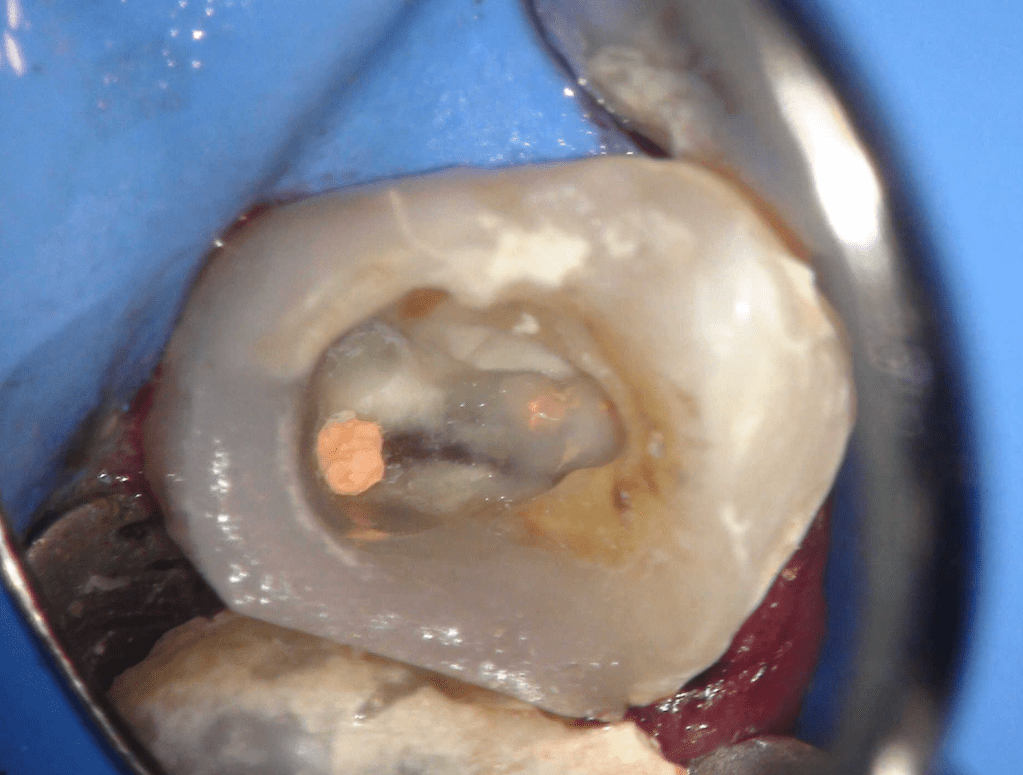

Pulpotomía biodentine + reco preendio